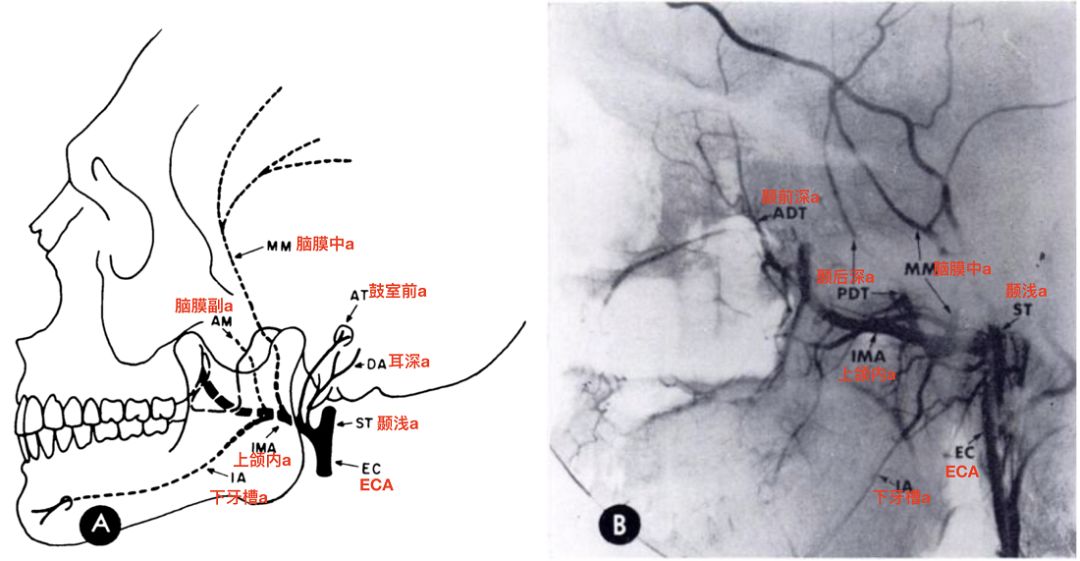

上颌内动脉的第一段(下颌段)模式图和脑血管造影,侧位观(Allen 1973)。

![]()

上颌内动脉第一段主要的分支包括:耳深动脉,鼓室前动脉,脑膜中动脉,脑膜副动脉,下牙槽动脉。

上颌内动脉第一段主要分支以及供血区(Alvernia 2017)。

3、上颌内动脉第一段的分支包括耳深动脉,鼓室前动脉,脑膜中动脉,脑膜副动脉,下牙槽动脉等。